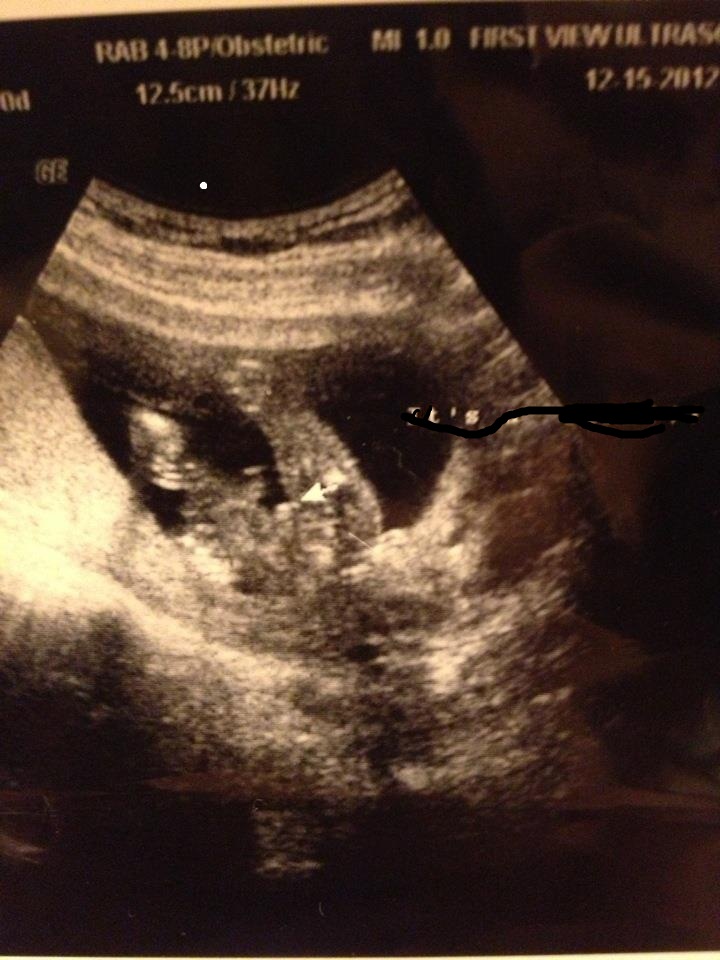

I had a 16 week ultrasound and tech said 100% but I'd love to have some reassurance! Thanks!!Attachment 7332